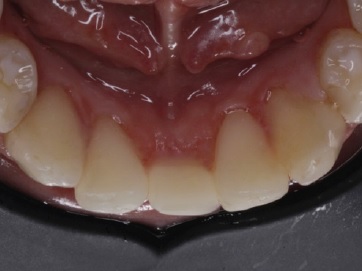

Figure 15 Case 2: Intraoral view after the extraction of the mandibular primary left central incisor and restoration of the mandibular primary right central incisor.